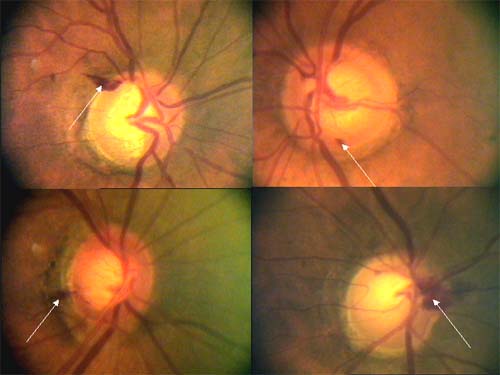

Lokalizovaný výpadek nervových vláken byl popsán poprvé teprve roku 1973 Hoytem. Je vějířovitého tvaru, připomínající ocas komety. Vyskytuje se u 20% glaukomů, není však pro glaukom specifický (drůzy, chorioretinální jizvy, dlouho trvající edém disku, pozánětlivá atrofie). Není u zdravých očí.

U glaukomu bývá v časných a středních stádiích, častěji u fokláního ischemického typu, v místech, kde byly před více než 2 měsíci peripapilární hemorhagie, kde exkavace je protažena k okraji terče a kde je rozsáhlejší peripapilární atrofie. Nebývá u pokročilého glaukomu. Airaksinen: výpadky předcházejí perimetrickým změnám.

Peripapilární hemorhagie u glaukomu

Charakteristika

Plaménkovité nebo třískovité hemorhagie na okraji terče jsou vyskytují u 4-7% pacientů s glaukomem, hlavně u počínajícího a středně pokročilého poškození zrakového nervu. U pokročilého glaukomu s totální ztrátou lemu se již nevyskytují. Nejčastěji jsou v horním a dolním temporálním kvadrantu terče. Ve dvou epidemiologických studiích byla nalezena frekvence hemorhagií na očích bez glaukomu jen v 1%. Tato vysoká specificita 99% je nám nápomocná k včasné diagnóze glaukomu a svědčí na jeho progresi. Peripapilární hemorhagie však nejsou specifické jen pro glaukom (přední ischemická neuropathie, trombosa centrální vény sítnice, hypertonitcká neuroretinopathie, diabetická retinopathie).

Patogeneze

Předpoklad, že posunem kribriformní laminy dozadu dojde k ruptuře povrchových krevních cév neobstojí před klinickou zkušeností, že při výrazném zvýšení tenze po kontusi oka tyto hemorhagie nevznikají. Také názor, že jde o ischemický proces, neodpovídá tomu, že u glaukomu nenacházíme vatovitá ložiska, typická pro infarkty ve vrstvě nervových vláken. Nevíme ani, zda krvácení pochází s arteriol, venul nebo z kapilár peripapilární radiální pleteně.

Průběh

Sonnsjo a spol. fotografovali po 14 denních intervalech po dobu 2

let terče s hemorhagiemi u dvou pacientů s glaukomem. Hemorhagie se

objevovaly znovu a znovu na stejném místě, což by mohlo způsobit

mylnou představu, že se hemorhagie jen pomalu resorbují. Krev

pronikala do periferie podél nervových vláken a po resorpci na disku

krev někdy ještě přetrvávala peripapilárně a působila dojmem

hemorhagie nesouvisející s terčem.

Hemorhagie můžeme nalézt u všech typů glaukomu, nejčastější jsou u

fokálního ischemického typu, méně časté u glaukomu s vyšší tenzí. Je

možné, že vyšší nitrooční tenze zastaví krvácení rychleji, takže

hemorhagie jsou u glaukomu s vyšší tenzí menší a rychleji se

vstřebávají. Naopak u glaukomu nízké tenze bývají větší a

vstřebávají se pomalu. Možná právě to je důvodem, proč hemorhagie

častěji vidíme u glaukomu s nízkou tenzí.

Asi po 2 měsících od vzniku hemorhagií dochází k výpadku svazečku

nerovvých vláken.